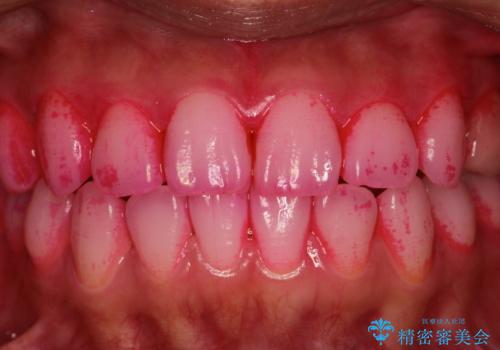

一見きれいに見える歯でも、染め出し(歯垢染色液)を使うとこのように歯と歯茎の境目や、歯と歯の間などに磨き残しがあることがわかります。歯磨きには、いつも気をつけているから磨き残しはナシと思っていても、実際完璧に磨ききることはなかなか難しいです。歯科医院にて、専門の機械で定期的なPMTCを行うことが大切です。